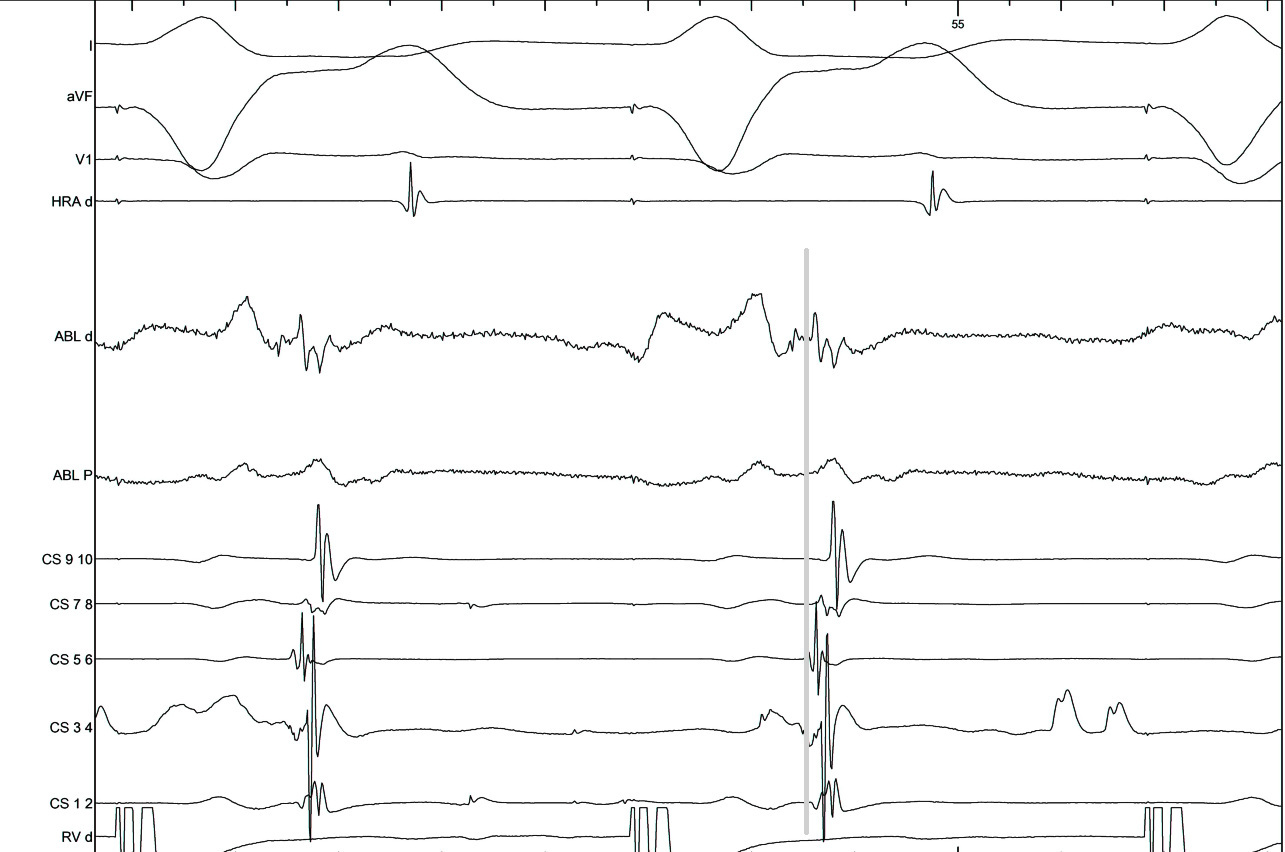

Mapping in diverticulum

diverticulum.jpg

med_lat_div.jpg

signals.jpg

Mapping in diverticulum - CSE potential most important

div_schematic.jpg

Selvaraj RJ et al. Radiofrequency ablation of posteroseptal accessory pathways associated with coronary sinus diverticula. J Interv Card Electrophysiol. 2016 Nov;47(2):253-259. doi: 10.1007/s10840-016-0113-x.